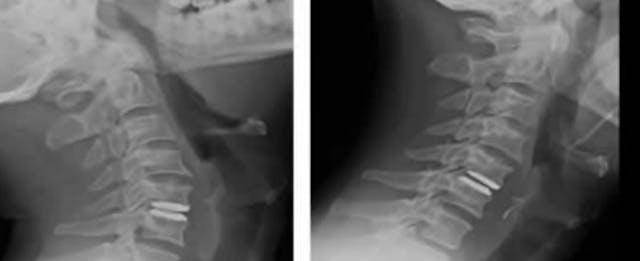

The video demonstrates an artificial disc replacement anteriorly with a prosthesis at the level of C5/6 in a 42-years old male with right sided radicular pain resistant to conservative treatment.